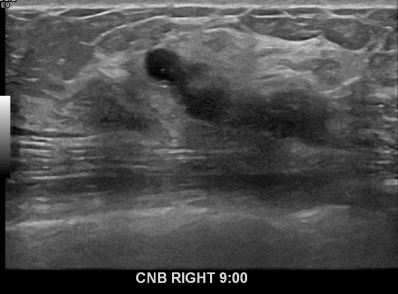

상기환자 외부검사상 이상소견으로 내원하신 30대여성으로 우측유방의 의심스러혹

조직검사시행해 유방암 진단되었습니다.